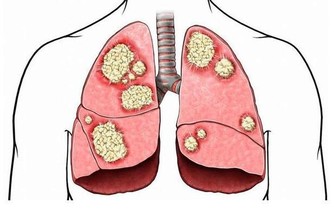

2.癌症

癌症也是這一年齡段高發的疾病,如肝癌、肺癌、乳腺癌、胃癌等。

出血

癌組織侵犯血管或癌組織小血管破裂而產生。如肺癌患者可能咯血或痰中帶血;胃癌、食管癌、結腸癌則可能嘔血或便血,子宮頸癌可能有陰道流血。